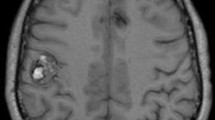

Cavernous malformations are compact masses of sinusoidal vessels without intervening brain parenchyma. They are angiographically occult and may have a developmental venous anomaly that is demonstrated by angiography. Familial cavernomatous malformations are common in Hispanic population and more often are multiple and transmitted by autosomal dominant mutations. Most of these lesions are not detectable by CT imaging. They may appear as hyperdense lesions with or without calcifications and acute hemorrhage. MR T2-weighted images, T2-weighted gradient echo (GRE) sequences (Figs. 6 and 7), and susceptibility-weighted imaging (SWI) sequences are the best sequences for detecting cavernomas. Cavernomas appear as popcorn lesions consisting of a reticulated heterogeneous core surrounded by a hypointense hemosiderin ring. GRE sequences demonstrate a prominent susceptibility effect (blooming), and SWI sequences show more smaller lesions than GRE sequences [34]. Acute hemorrhage can show surrounding edema on T2-weighted images. Cavernomas are classified as four types: I, hyperintense on both T1 and T2 sequences; II (classic), mixed hyperintense and hypointense core surrounded by a hypointense core on T2 sequences; III, hypointense on both T1 and T2 sequences; and IV, hypointense only on GRE and SWI sequences and these are usually asymptomatic [35]. MR tractography, especially of the corticospinal tract, may facilitate surgical removal of these lesions in periventricular or brainstem locations by allowing the surgeon to plan safe trajectories that avoid the corticospinal tract in order to approach these lesions.